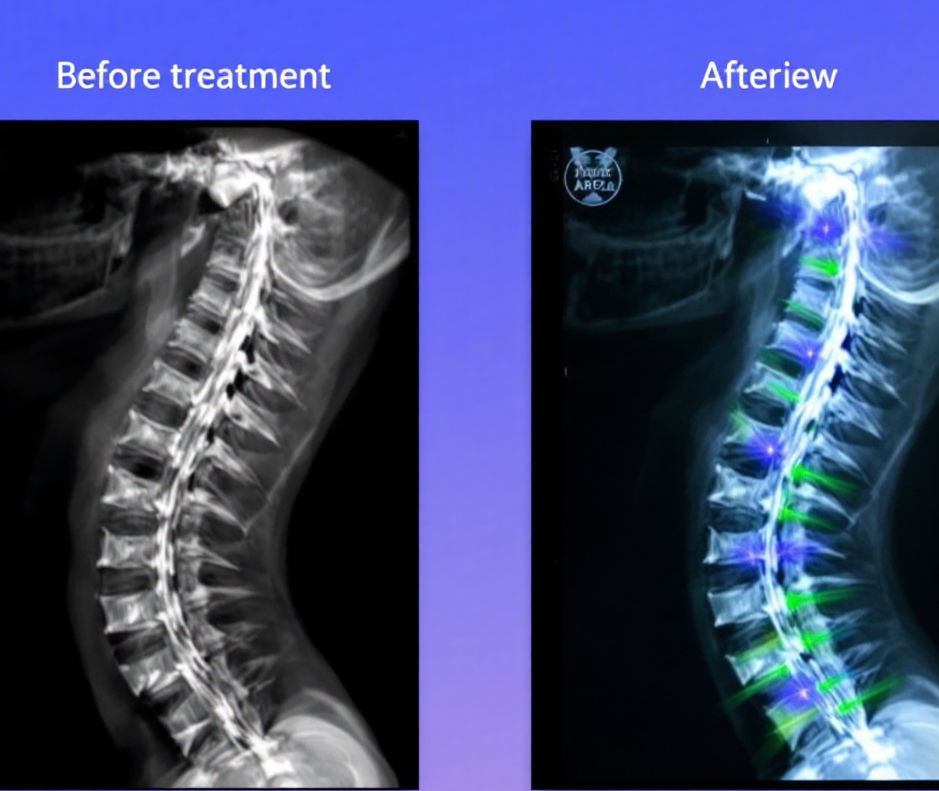

추나요법은 한의학 기반의 도수 치료법으로, 디스크 환자에게도 적용되는 보완적 치료입니다. 하지만 모두에게 효과적인 것은 아니며, 증상과 영상소견에 따라 선택이 달라질 수 있습니다. 오늘은 디스크 환자가 추나요법을 선택할 때 알아야 할 핵심 정보를 정리해드립니다.

전통 한의학 기반의 수기 치료로, 척추와 관절의 배열을 교정하여 통증을 완화하는 방법입니다.

MRI 등 영상자료와의 병행 해석이 필요합니다.